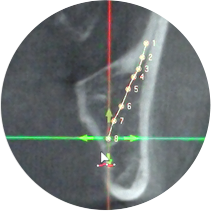

신경손상 걱정 없도록

개인별 신경 주행경로 확인!